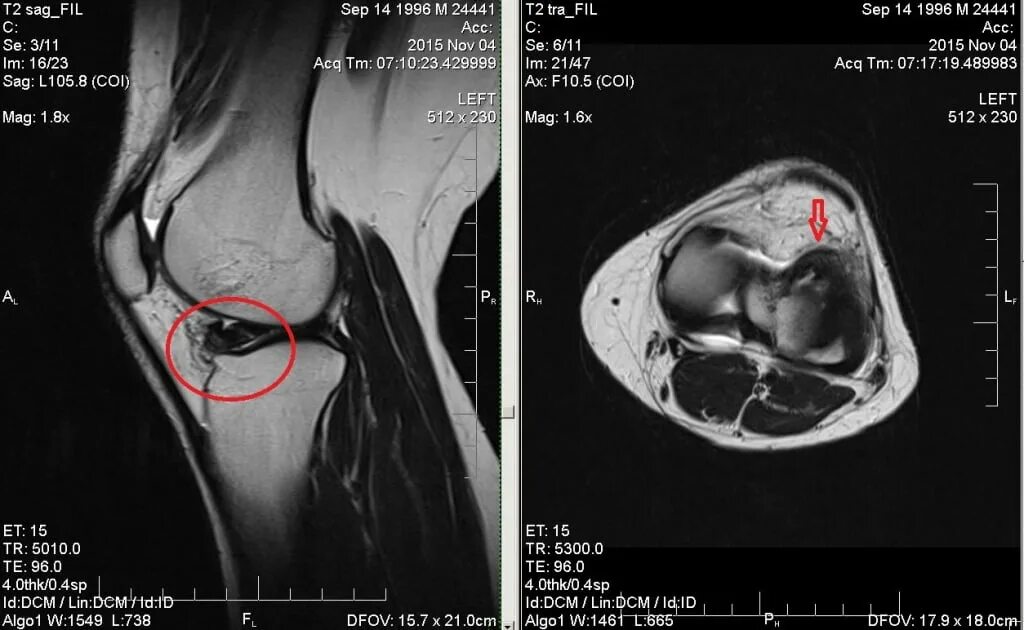

Повреждение мениска мрт